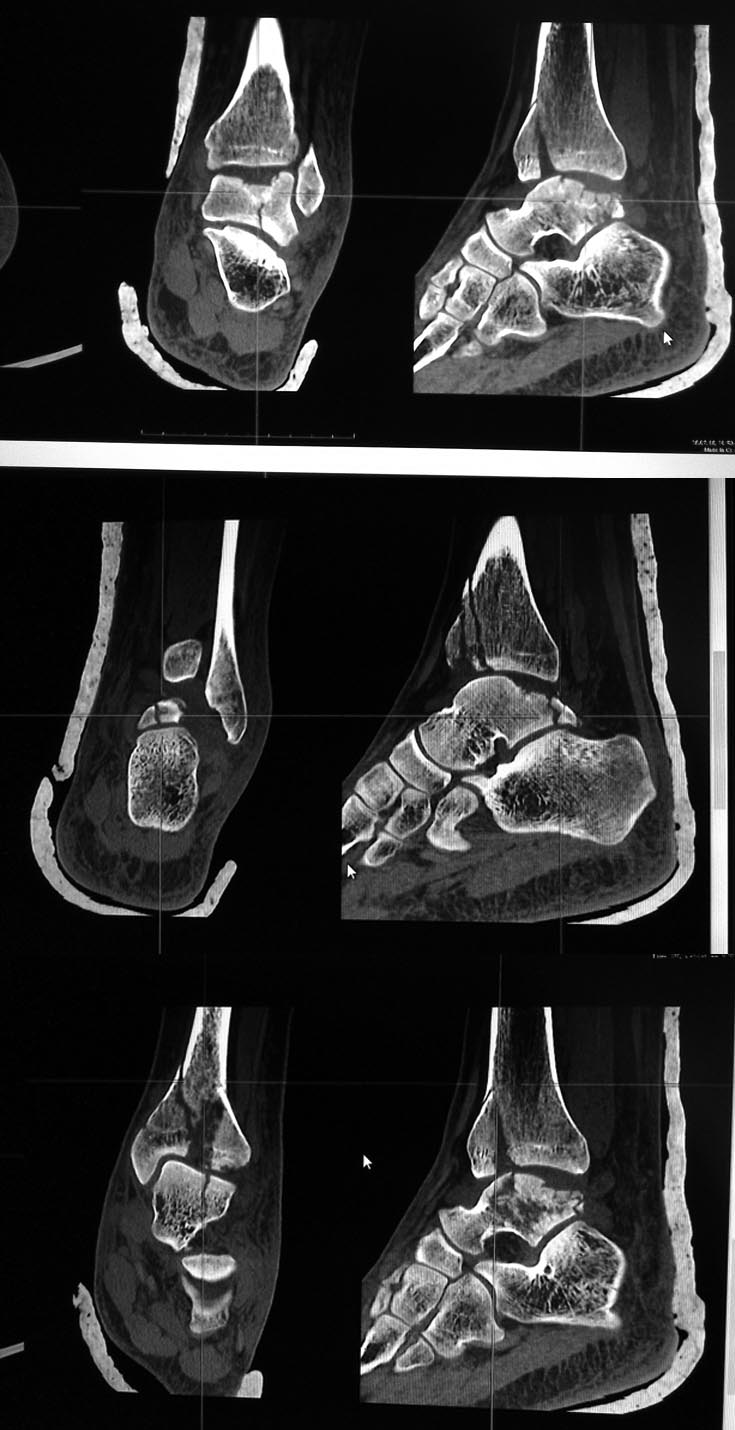

Re: перелом таранной кости и пилона

Кирилл, проблема ведь не только в таране, пилон тоже пострадал, ведь так? Дайте дистракцию на аппарате, может за счёт лигаментотаксиса что то встанет. А там подумать. Но напрашивается фиксировать передник край б/б кости, и затем добраться к тарану, доступ по данным срезам продумать сложно, может потребуется остеотомия наружной лодыжки, отломки тонким долотцом поднять, костная пластика дефекта, винты, в послеоперационном периоде опять аппарат. Уж больно куском много. Артродез то же не исключаю.

С пилоном тактика ясна, аппарат сразу не накладывал из-за приличного состояния мягких тканей и умеренного отёка, доступ к таранной кости возможно удастся через зону перелома пилона. А вот как зафиксировать фрагменты суставной поверхности тарана после репозиции?

Очень сложный перелом. И срезов маловато. Наверное нужно подумать над доступом, который позволит использовать имеющуюся линию перелома для подхода к суставной поверхности таранной кости. Через это доступ "поднять" вдавленные фрагменты с последующей костной пластикой образовавшихся пустот. Выполнить остеосинтез таранной кости винтами. И закончить остеосинтезом большеберцовой кости.

поверьте, среди нас мало экспертов переломов таранной кости, ещё меньше - экспертов именно ТАКИХ переломов, а вот сочетание именно такого перелома с переломом пилона типа В - уж совсем редкость.

И так. Первым этапом я бы выполнил остеосинтез пилона с использованием подходящей передне-внутренней пластины в качестве опорной. Это позволило бы мне сформировать "матрицу", по которой, возможно, придётся моделировать суставную поверхность таранной кости. Далее из наружного (задне-наружного) доступа с остеотомией малоберцовой кости я бы подошёл к тарану. Вполне возможно, что сформировал бы порт по наружной поверхности его блока и потихоньку "выстучал" отломки по восстановленной суставной поверхности б/б кости. С фиксацией или опорной минипластиной, или винтами 1,5, максимум 2 мм. По ситуации. Всё должно быть под рукой